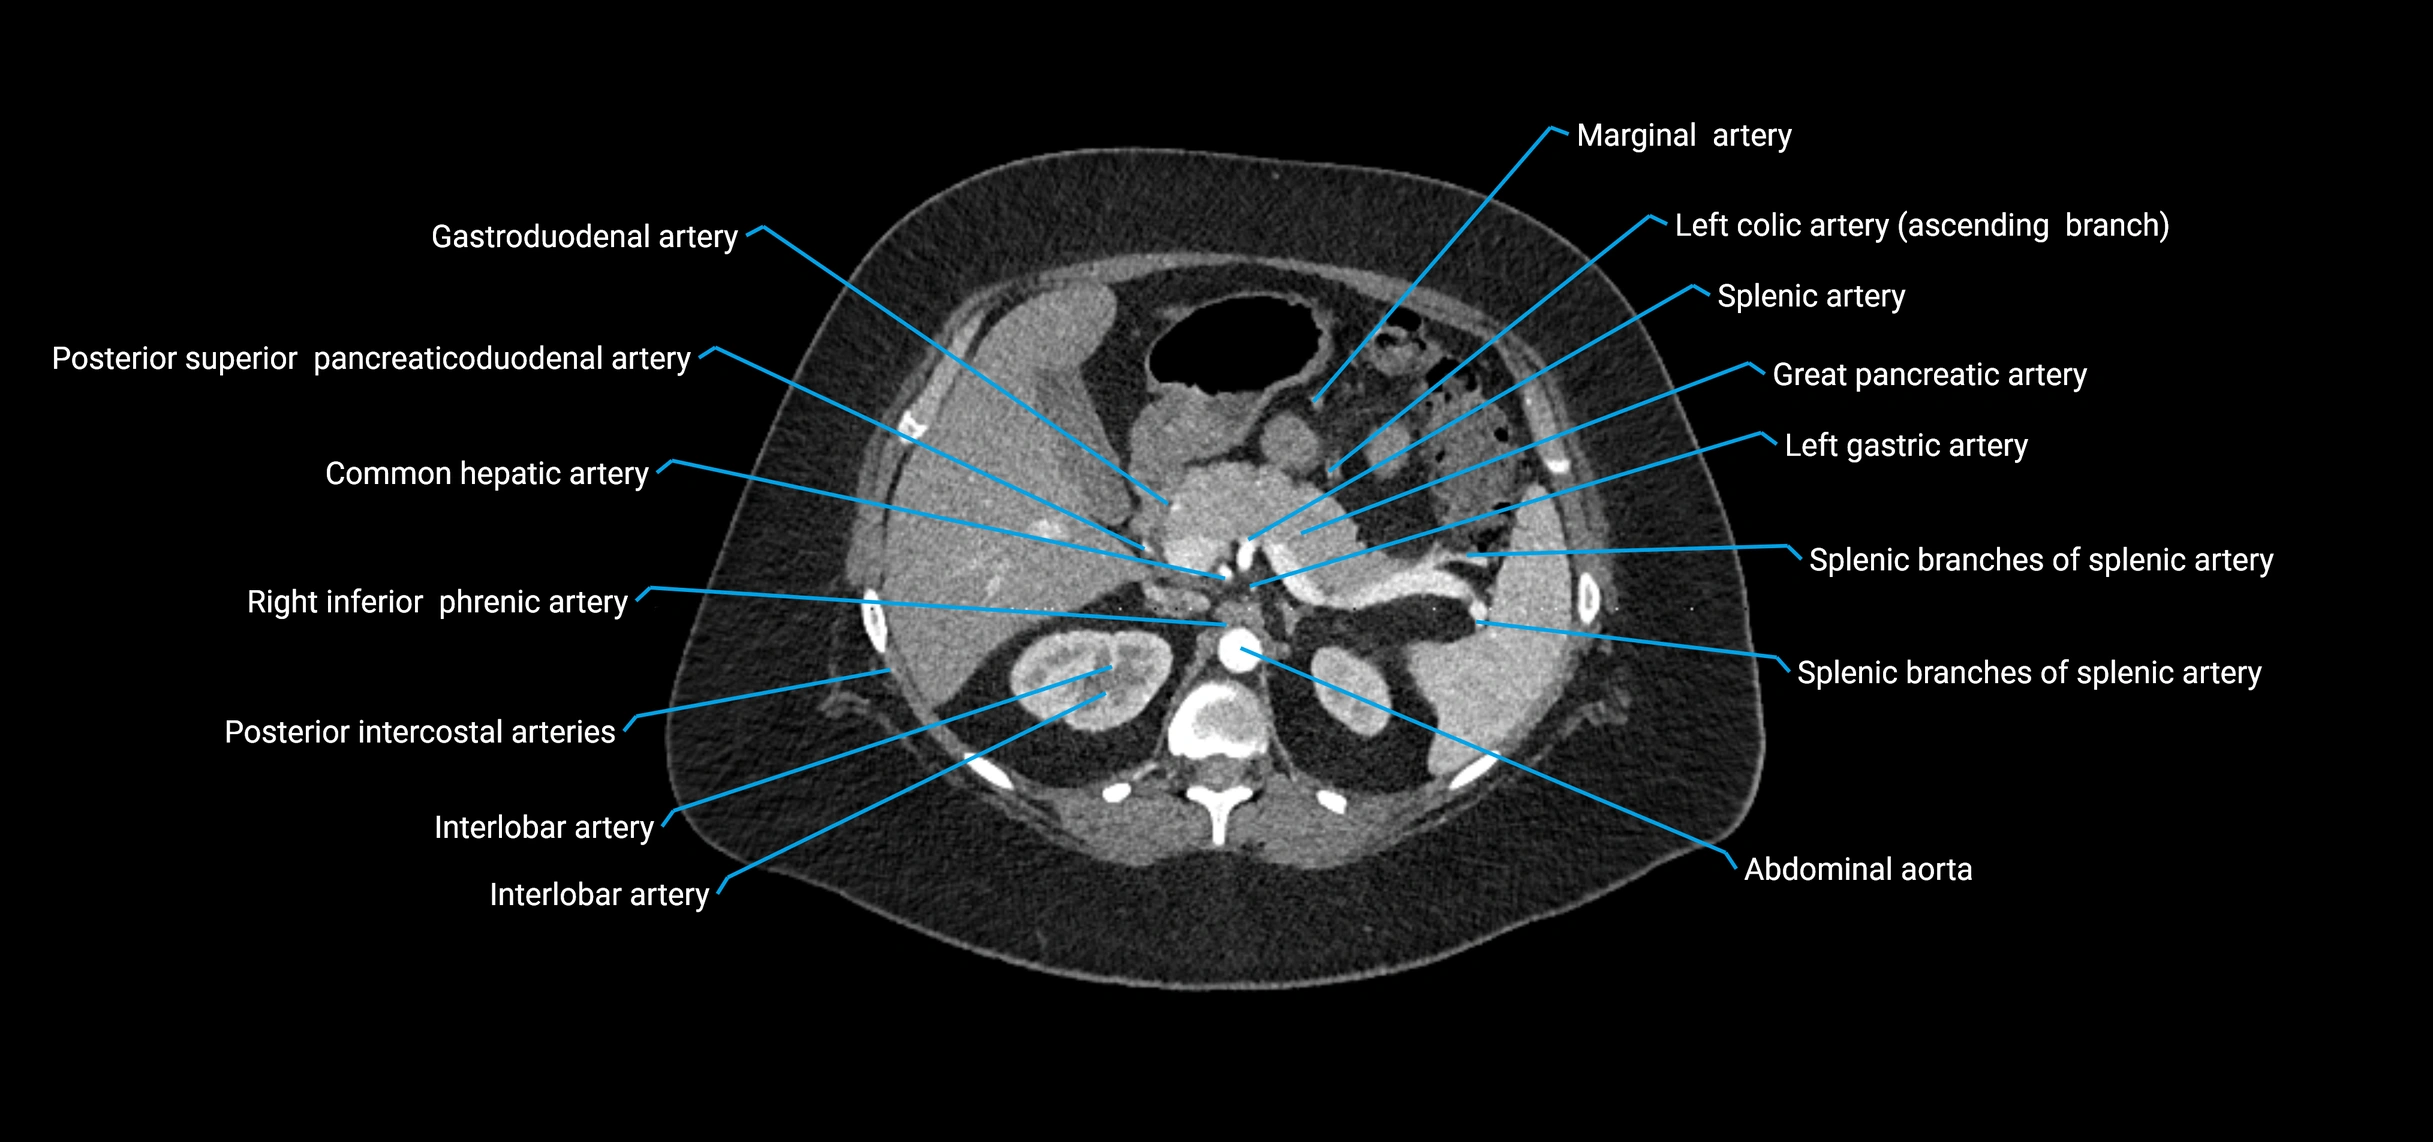

CT images

image

Contrast-enhanced CT (CTA):

• Gold standard for abdominal aortic imaging

• Provides excellent detail of lumen, wall, aneurysm, thrombus, and branch vessels

• Multiplanar and 3D reconstructions help in aneurysm measurement, stent graft planning, and dissection evaluation